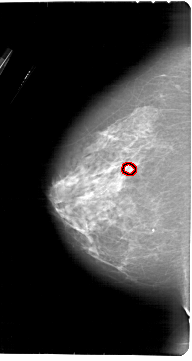

A_1913_1.LEFT_CC

FILE: A_1913_1.LEFT_CC.OVERLAY

TOTAL_ABNORMALITIES 1

ABNORMALITY 1

LESION_TYPE CALCIFICATION TYPE PLEOMORPHIC DISTRIBUTION CLUSTERED

ASSESSMENT 4

SUBTLETY 4

PATHOLOGY BENIGN

TOTAL_OUTLINES 1

BOUNDARY